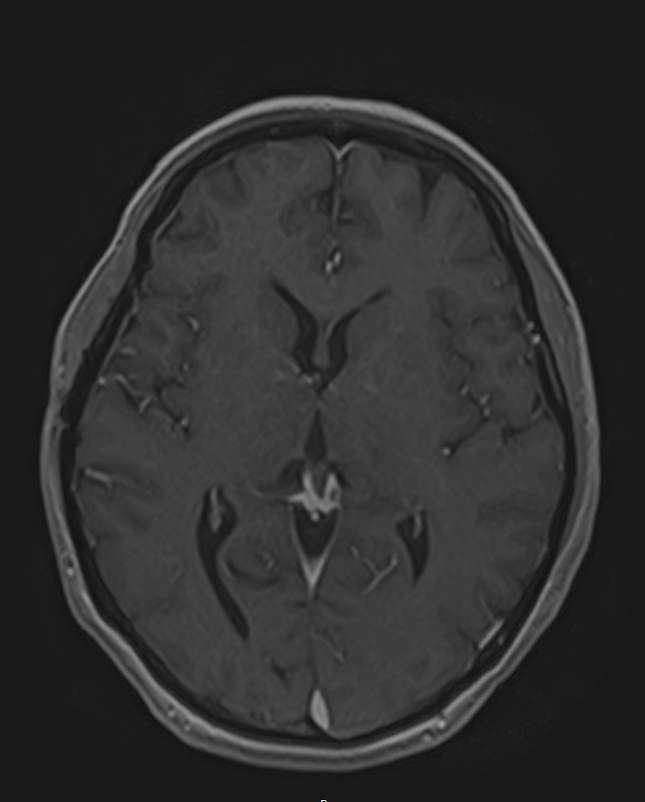

МРТ головного мозга с контрастированием – методика проведения магнитно-резонансной томографии, при которой внутривенно вводится препарат, содержащий гадодиамид (соли металла гадолиния). Контрастное вещество не проникает через гемато-энцефалический барьер и в норме не накапливается в тканях головного мозга. Однако при нарушении его целостности способно накапливаться в патологических очагах, в частности, в опухолях, зонах воспаления и участках демиелинизации нервных волокон.

Это способствует ранней диагностике заболеваний головного мозга, таких как рассеянный склероз, доброкачественные и злокачественные новообразования. Кроме того, с помощью контраста можно оценить степень и характер васкуляризации патологического процесса.

Исследование в нашей клинике выполняется на современном высокопольном томографе экспертного класса TOSHIBA VANTAGE TITAN 1,5 Тесла, который использует разные режимы сканирования с толщиной среза от 1мм в различных плоскостях с последующей цифровой обработкой полученных данных для создания трехмерных изображений. Аппарат позволяет выявлять структурные изменения в веществе головного мозга уже на начальной стадии, когда другие методы не дают результатов.